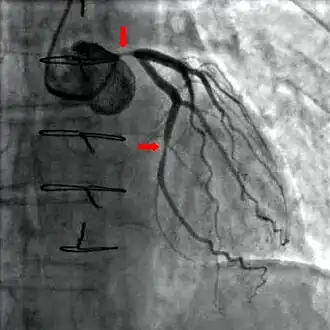

![]() Cateterismo de coronárias mostrando oclusões no ramo principal da artéria coronária esquerda (seta superior) e a artéria descendente anterior esquerda (seta inferior). |